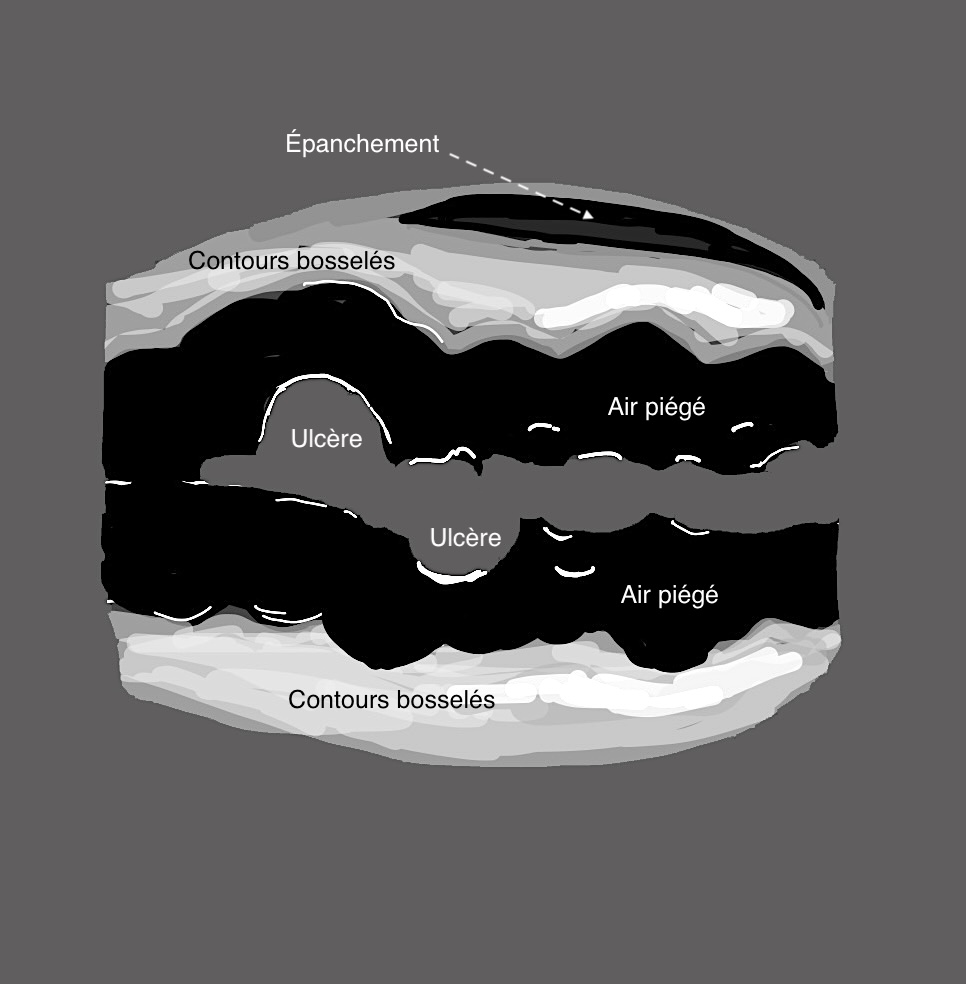

En échographie la colite aigüe grave se traduit par

1. Epaississement important :

une inflammation au delà de 8 mm, voir 10 ou exceptionnellement 12 mm est un signe de gravité.

2. la disparition de la structure en couches

L’inflammation qui dans la RCH est au départ superficielle (couches 2 et 3) gagne la totalité de la paroi (la sous muqueuse devient hypoéchogène et toute la paroi devient noire hypoéchogène)

Si l’inflammation s’aggrave, on peut voir des ulcères creusants en surface et la limite externe de l’anse (classiquement rectiligne dans la RCH) devient irrégulier, bosselé.

3. L’inflammation atteint la périphérie de l’anse donc

– hyperactivité doppler intense de la paroi et de la graisse (Limberg 3)

– présence de liquide en périphérie de l’anse (perforation imminente)

La paroi du colon devient totalement déformée, en surface avec ulcères, en périphérie avec des bords externes irréguliers, la graisse est infiltrée, voire apparition d’un épanchement liquidien, signe de gravité extrême